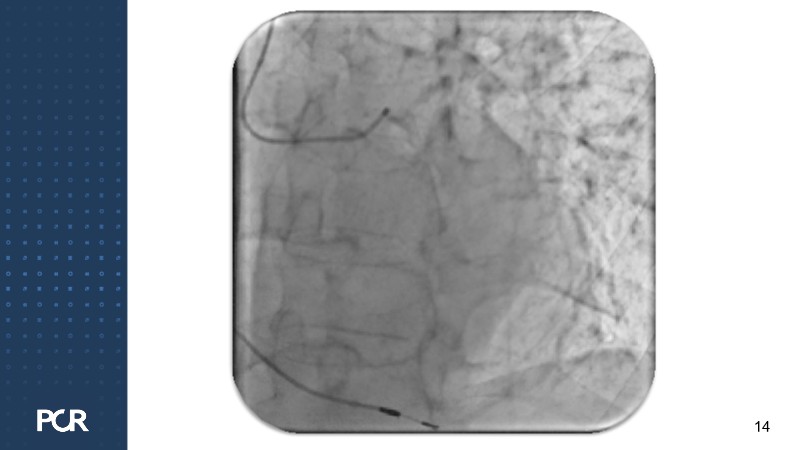

This session offers a comprehensive overview of the management of high bleeding risk (HBR) patients with multivessel disease. Through expert discussion and a live case demonstration featuring a complex elderly patient, it highlights how intracoronary imaging and physiology can guide procedural decisions and improve outcomes in this vulnerable population. The session also explores PCI strategies adapted to bleeding risk profiles, with a particular focus on the live case approach, including the use of sirolimus-eluting stents to optimise both procedural safety and long-term results.